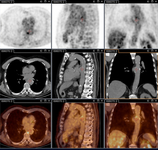

Q fever aortic mycotic lumbar aneurysm diagnosed at PET scan: 18F-fluorodeoxyglucose PET/CT. In this asymptomatic patient with heart valve history with elevated serology, the PET scan diagnosed an aortic endocarditis on native valve with thoracic and lumbar aortic mycotic aneurysms

Institut Hospitalo-Universitaire Méditerranée Infection (patient consent obtained)

Q fever aortic mycotic thoracic aneurysm diagnosed at PET scan: 18F-fluorodeoxyglucose PET/CT. In this asymptomatic patient with heart valve history with elevated serology, the PET scan diagnosed an aortic endocarditis on native valve with thoracic and lumbar aortic mycotic aneurysms